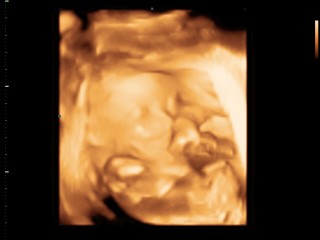

ใบซาวด์

ขอดูใบซาวด์เเม่ๆคลอดเดือนก.คหน่อยค่ะได้ผญหรือผชกันค่ะ

หญิงจ้า23+3

ได้หญิงจ้า